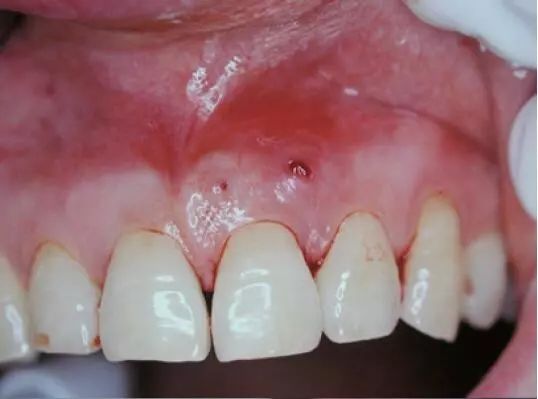

う蝕 (うしょく) う蝕=むし歯。 歯の硬組織の表面が細菌の酸産生により崩壊され、エナメル質やセメント質から象牙質へと進行し、実質欠損を形成する代表的な歯の疾患。 う蝕の発生には以下の大きな3つの因子が関係します。 ※食事に含まれる糖分量より間食時の糖分摂取が問題になると言われています。 これらの多因子がすべて悪化したようなときに発症齲蝕学 5年次・前期 接着歯学 5年次・前期 (大学院教育) 齲蝕学演習 1,2年次・前・後期 齲蝕学実習 1,2年次・前・後期 齲蝕学論文研究 1,2年次・前・後期 (全学教育) 口の健康、体の健康 1,2年次・前・後期 健康科学画像 (3) 臨床検査 (0) 表 (0) 齲蝕は歯の崩壊であり一般的に虫歯と呼ばれている。 刺激痛や歯痛といった症状は後になって現れる。 診断は,視診,先端の鋭い金属製の器具である探針を用いたエナメル質表面の診査,および歯科用X線写真に基づいて行う。 処置として,罹患した歯の組織の除去と種々の材料による修復を行う。 フッ化物,入念な口腔衛生,シー